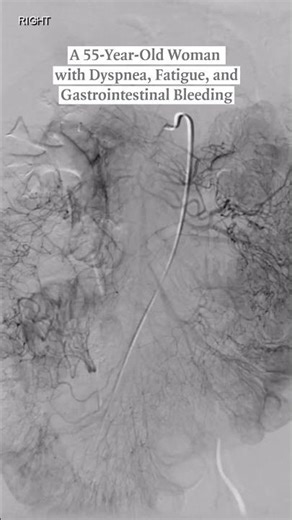

- Angiography

Angiography - Renal